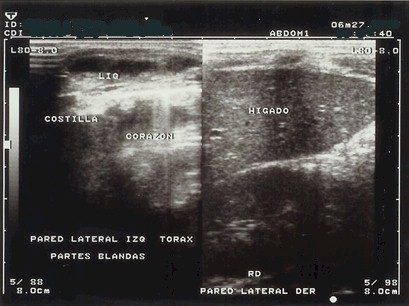

Se realizaron además estudios de hemoaglutinación indirecta para amiba se reporto positiva con títulos 1: 4096, ya con el diagnostico antes planteado pusimos tratamiento endovenoso con metronidazol a la dosis de 15 mg/Kg. de peso corporal como dosis de impregnación, y se continuo cada 8 horas con 7.5 mg/Kg. de peso, durante diez días de tratamiento, al cabo del mismo sin aparecer otras complicaciones como ruptura del absceso se realizo ecosonografía de control la cual fue normal figura (3), y los estudios hematológicos mejoraron en su totalidad persistiendo las transaminasas algo elevadas .

Figura (3)